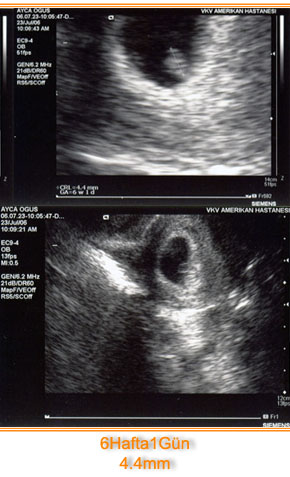

4 Hafta – İlk Tanışma

Bugün seninle ilk tanışmamız ve seninle beraber hayatımıza giren Dr. Alper Mumcu‘yla ilk tanışmamız.Ben bugün doktora giderken senin 6 haftalık olduğunu düşünüyordum. Odaya girip biraz sohbet ettikten sonra kalbim ata ata seninle tanışmak için içeriye gittim ve sonra birden baktım ki küçücük siyah bir nokta var ekranda, tabii ben seni...